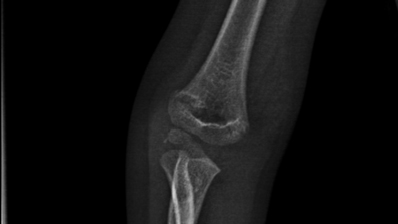

一位4岁小女孩因不慎摔伤导致右肘部肿痛被家长带来我院骨科就诊,经过检查后诊断为“右侧肱骨远端骨折”,因骨折有移位且对位不佳,建议行手术治疗。

骨折部位术前